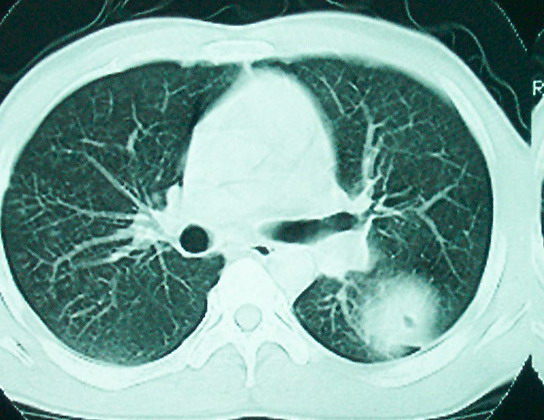

m      37y      发热   咳脓痰月余      ct肺脓肿但住院抗炎治疗后双肺内结节不知该如何解释

治疗后见左肺下野病灶较前缩小但双肺内结节影似无变化请较各位老师该如何下结论    治疗前wbc14.5 治疗后wbc 11.0

血源性肺脓肿,一般由原发感染灶引起脓毒败血症,在肺部形成小脓肿,病变变化快,容易形成肺气囊,脓气胸,主要与转移瘤鉴别,通过临床病史可分

结合临床发热,咳痰考虑为血源性肺脓肿,不过双肺结节又在肺的边缘,还是小心一点,抗炎后复查吧

左下肺病灶除了明显的厚壁空洞 气液平外,明显见壁结节,另两肺多发小结节,综合考虑:左下肺周围性肺癌伴肺内转移.

除了肺内多发结节和左肺下叶的浓疡病灶,还应注意满肺散在的小结节影,还有右上肺前段支气管内膜不光整这些细节,结合病史,肺内多发结节应考虑结核性肉芽!